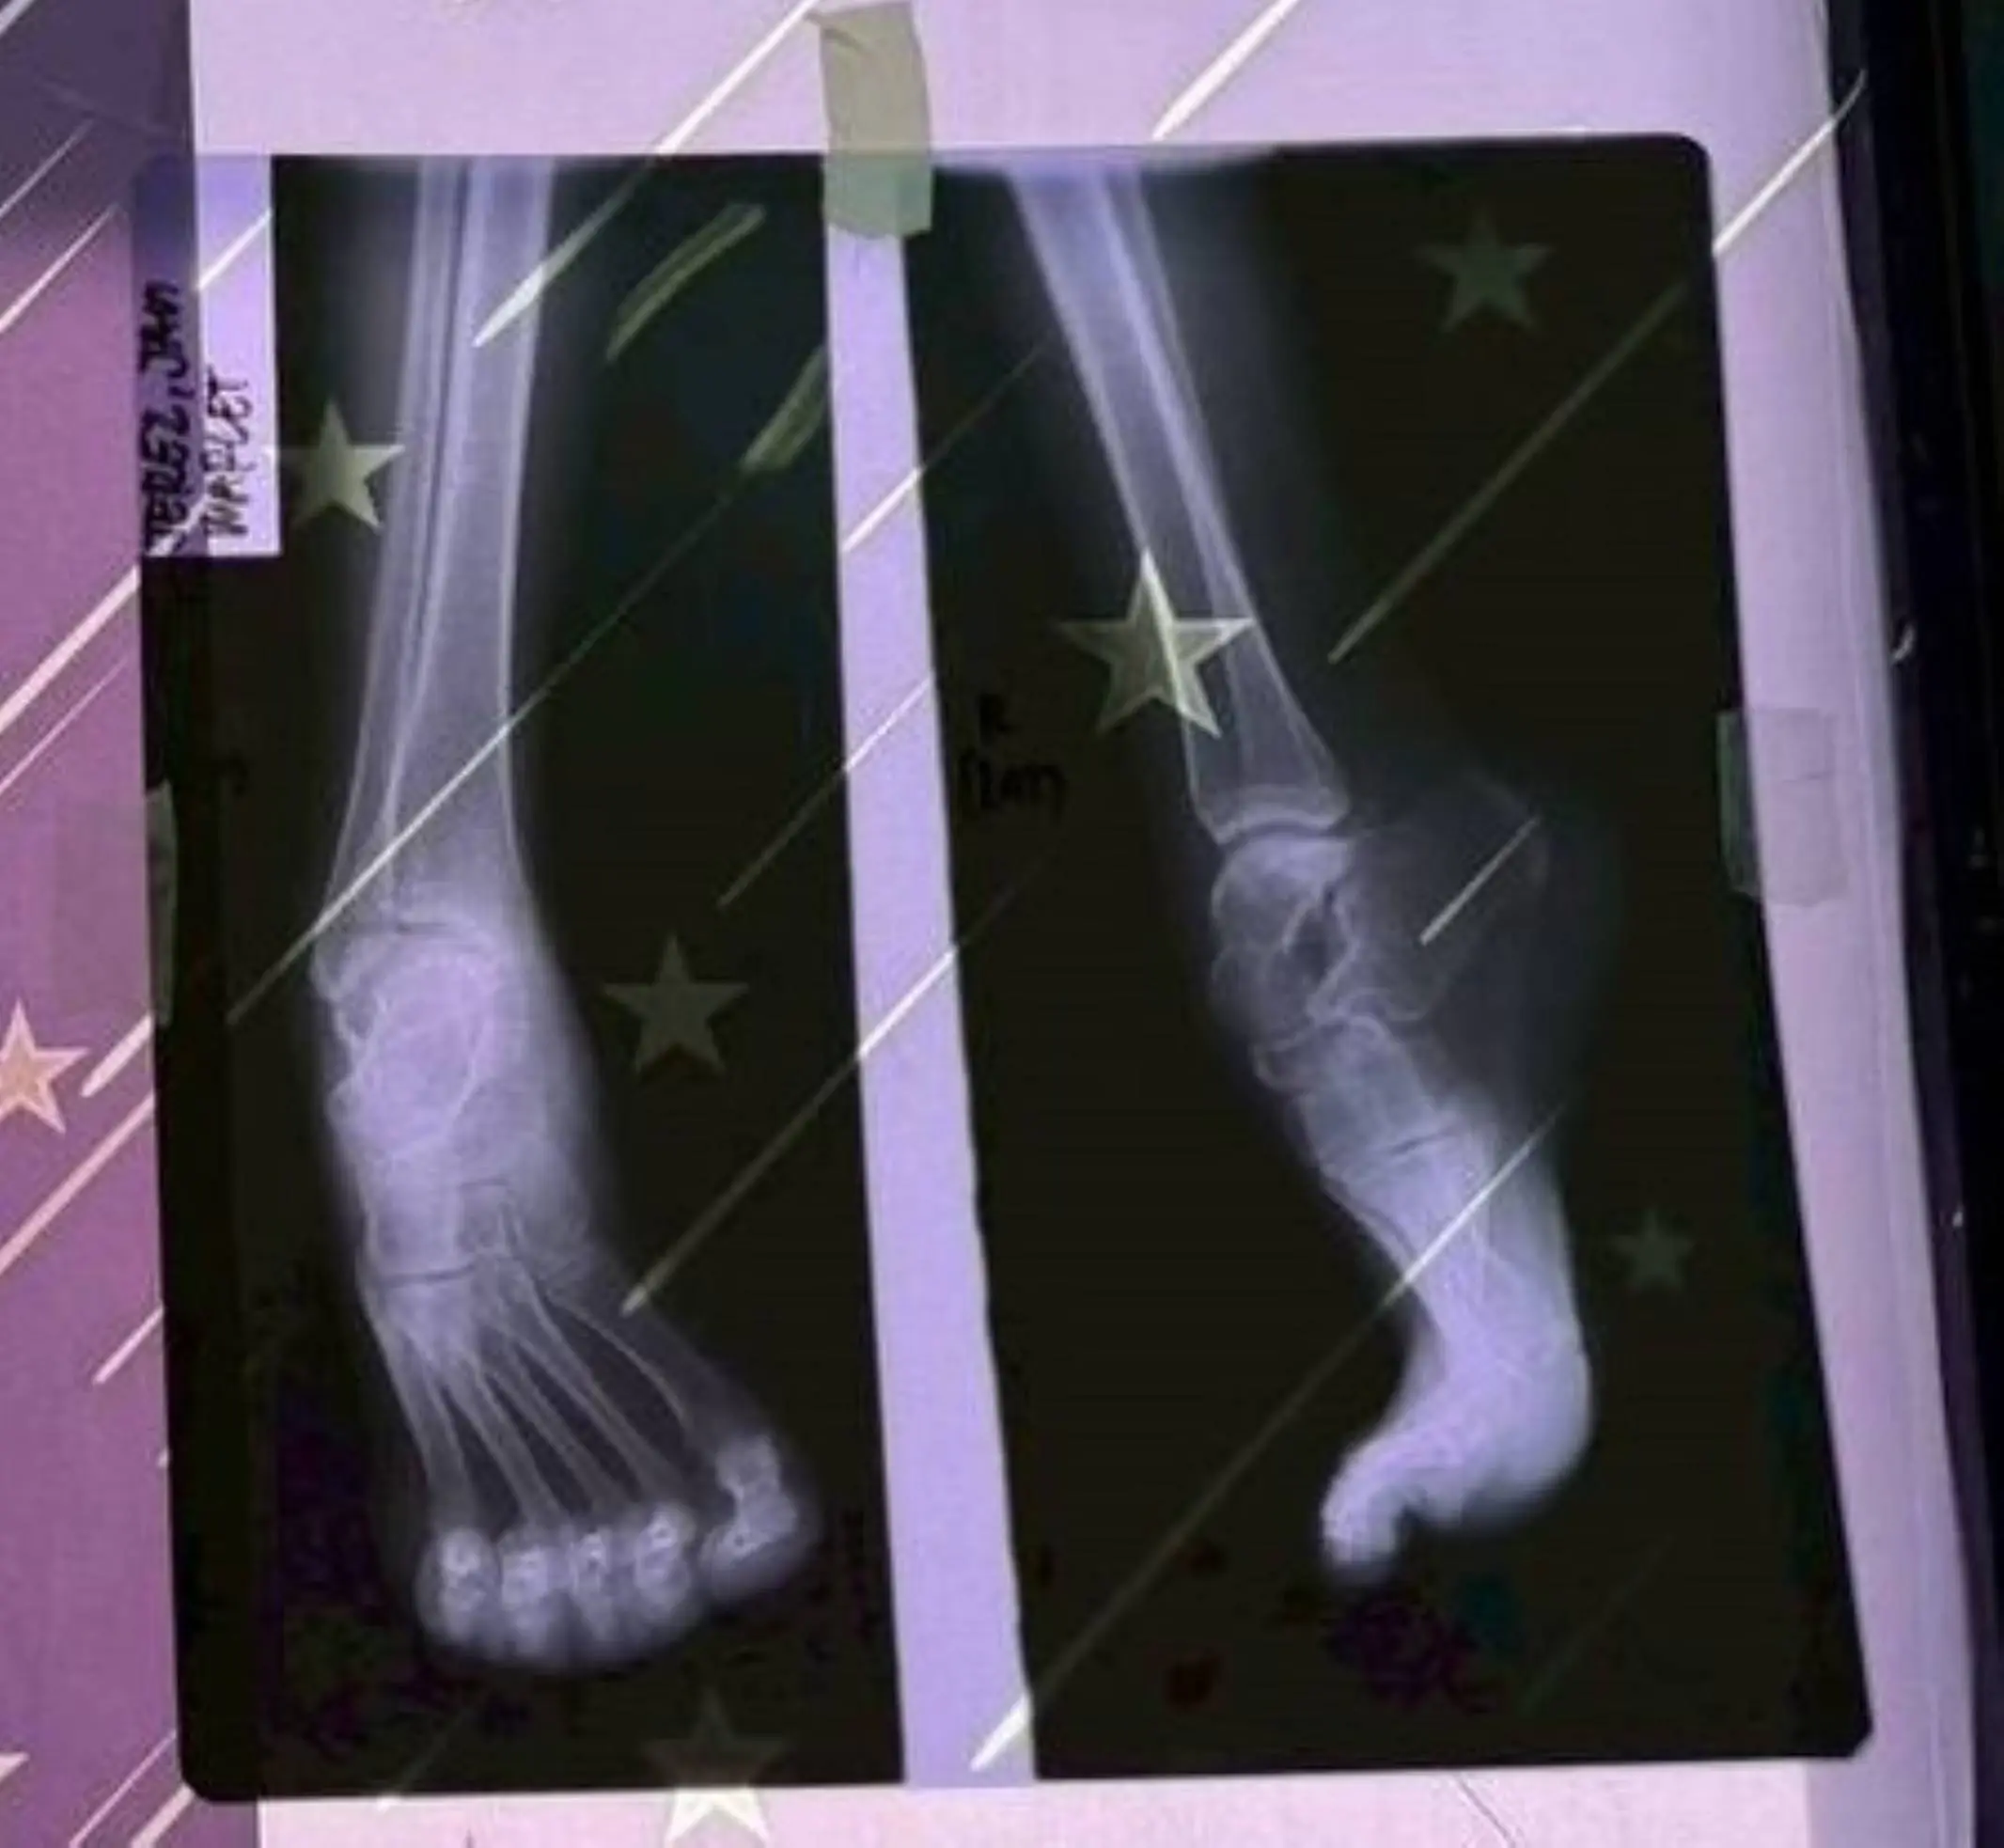

少女足部X光片

此次義診行動中,一名患有足部畸形的少女格外牽動醫療團隊的心。嘉基團隊在2025年短宣行動時首次見到她,因先天足部結構異常,她長期行走困難,也因外觀差異而缺乏自信,生活與求學都受到影響。醫療團隊返台後即開始規劃後續醫療協助,並在此次行動中攜帶更完整的設備與專業人力,為她進行足部矯正手術。

手術順利完成後,少女的足部外觀明顯改善,也有助於提升未來行走與日常生活能力。醫療團隊表示,希望透過這次手術,為她的人生帶來新的契機。隨著術後逐步恢復,她也將有機會重新回到校園,展開新的學習與生活。